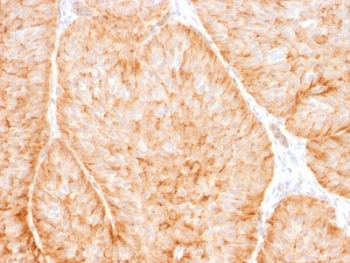

IHC staining of FFPE human esophagus tissue with SLC2A1 antibody (clone GLUT1/7308). Inset: PBS used in place of primary Ab (secondary Ab negative control). HIER: boil tissue sections in pH9 10 mM Tris with 1 mM EDTA for 20 min and allow to cool before testing.